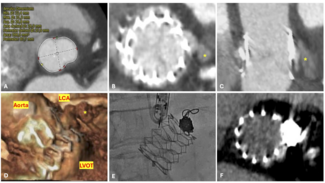

Based upon competitive flow noted during native vessel angiography, internal mammary graft patency was expected. Surprisingly, the LIMA was found to be proximally occluded (Figure 2). To reconcile the apparent discrepancy, exploration was performed for alternate sources of LAD filling. It was found that the LIMA downstream of the occluded origin filled via a single branch arising directly from the ipsilateral thyrocervical trunk (Figure 3, Video 2). The etiology of the proximal LIMA occlusion remains uncertain, but conceivably could have been related to vessel injury during coronary artery surgery. Regardless, an initial conservative strategy was felt appropriate, with the possibility of percutaneous intervention (native vessel or graft), or repeat CABG in the future, if required.

Based upon competitive flow noted during native vessel angiography, internal mammary graft patency was expected. Surprisingly, the LIMA was found to be proximally occluded (Figure 2). To reconcile the apparent discrepancy, exploration was performed for alternate sources of LAD filling. It was found that the LIMA downstream of the occluded origin filled via a single branch arising directly from the ipsilateral thyrocervical trunk (Figure 3, Video 2). The etiology of the proximal LIMA occlusion remains uncertain, but conceivably could have been related to vessel injury during coronary artery surgery. Regardless, an initial conservative strategy was felt appropriate, with the possibility of percutaneous intervention (native vessel or graft), or repeat CABG in the future, if required.

Discussion. The non-grafted LIMA can serve as a source of collateral supply to native coronary vasculature2 and peripheral arterial circulations.3 Anatomic variation in the LIMA is common, with an origin from a common stem with the thyrocervical trunk in greater than 8% of patients.4 However, external collateralization of an occluded LIMA has not been previously described. Given the prevalence of LIMA use in CABG, it is critical to be aware of unusual configurations, including collateralization of a proximally occluded LIMA graft as described in this report.